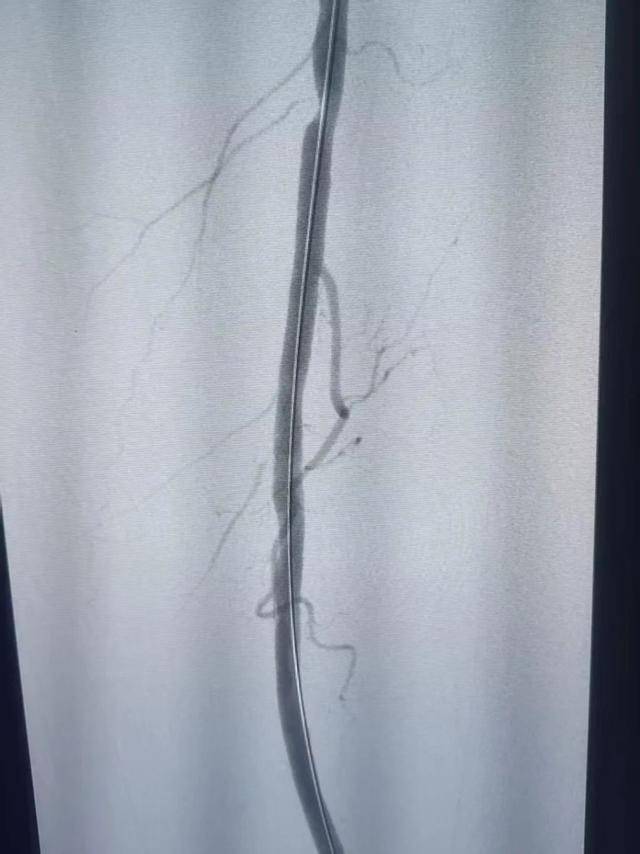

据了解,此次手术采用局部麻醉,术中患者完全清醒,仅通过大腿处一个3mm针眼,历时1小时顺利开通病变血管,术后造影显示血流通畅,术后下肢皮肤温度即刻回升,足背动脉搏动可触及。血管外科主任王晋军术后与患者交流病情时说,按照传统手术方法,最少要放3-4个支架,血管外科团队采用减容技术后,最终以零支架植入的方式完成了上述手术。

手术前

手术后